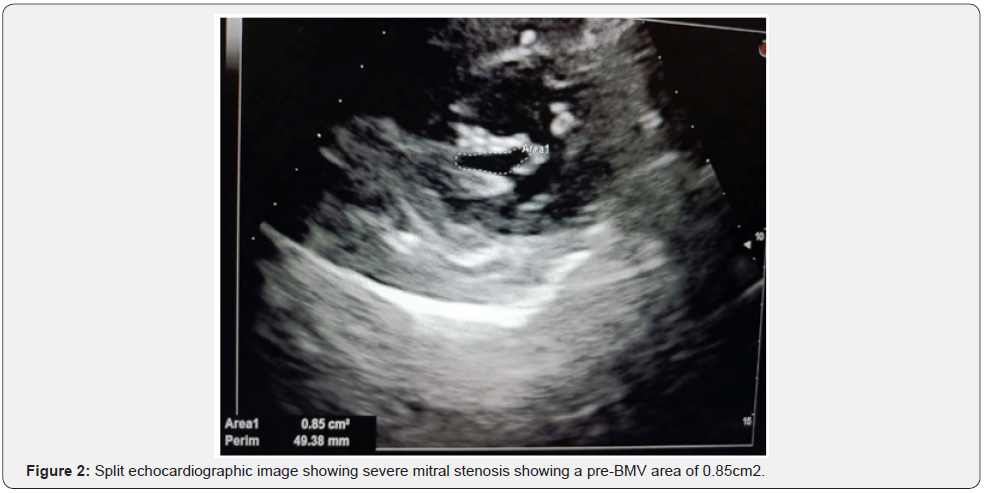

She was diagnosed with severe MS and a valve area of 0.85cm2 and after BMV valve area increased to1.5 cm with the commissures completely split and the patient was discharged on day 3 of post-BMV (Figure 2). The gradient across the mitral valve which was 32mms Hg came down to 2-3 mms Hg immediately after the procedure (Figure 3). The mean pulmonary artery pressure before BMV was 58 mmsHg, which came down to 32 mmhg. LA pressure before BMV was 42/26 mmHg and post BMV was 18/07 mmHg (Figure 4). There was minimal mitral regurgitation and no significant aortic valve disease. There was no vegetation or a clot seen on the transthoracic echocardiography. The left ventricular function was normal.